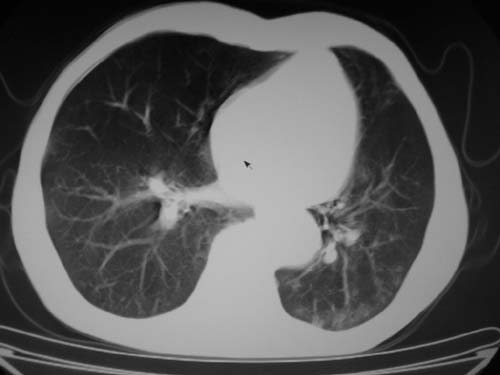

标题: CT19736:男,76岁,咳嗽,胸痛 [打印本页]

标题: CT19736:男,76岁,咳嗽,胸痛

支持左上肺周围型肺癌性并空洞形成伴胸椎转移。

空洞内壁有多发结节,支持癌性空洞。

支持左上肺周围型肺癌并空洞形成伴胸椎转移。z左下肺炎